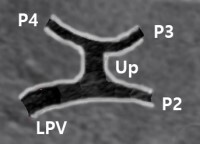

portal vein branch가 H 모양으로 보이도록. "Recumbent H"